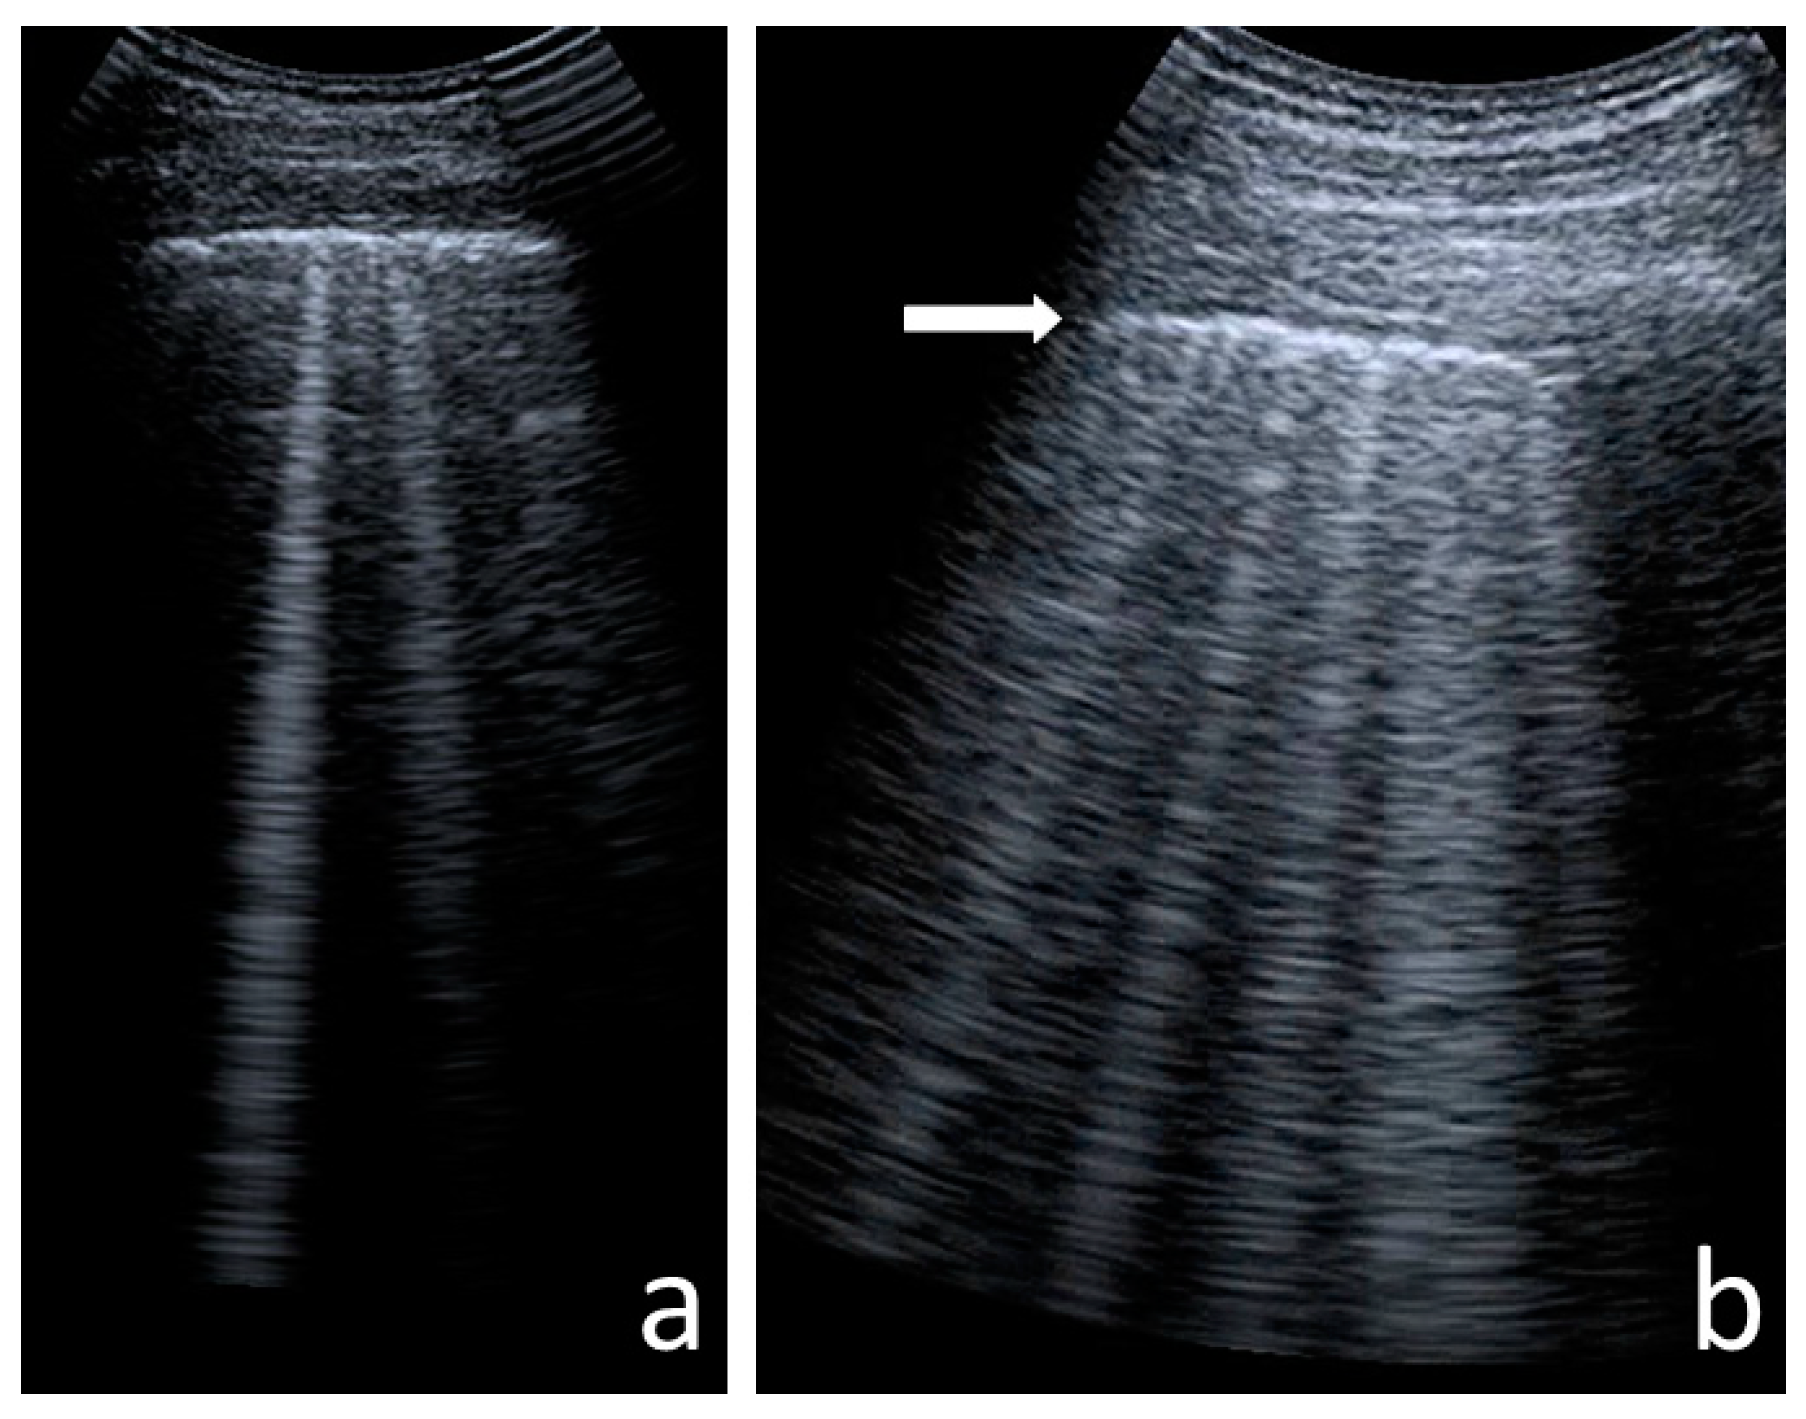

- Consolidations—hypoechoic, tissue-like areas: (a) small (≤10 mm) (Figure 6), and (b) major (>10 mm) (Figure 7); usually, major consolidations have the following associated features: the loss of pleural line echogenicity over the area of consolidation, absence of A-lines, presence of dynamic or static air bronchogram/air trapping and vascular pattern (in CD option) within the area, C-lines below the area, B-lines surrounding it [17,31];